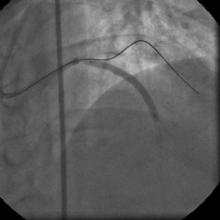

The left system was engaged with XB 3.5 guiding catheter through the femoral route. With the help of a 1.1x1.5mm CTO balloon, we directed a Shinobi guidewire towards the ostial LAD lesion (Figure 4). After making sure that the guidewire was pointing towards the CTO with its tip at the CTO lesion, we used the torquer to gently twirl the guidewire without forcing or overly manipulating it and allowed the guidewire to find its own way through the CTO by patiently twirling it at the lesion site. Within a few minutes, the guidewire jumped through the CTO lesion (Figure 5) and then through the lesion with the help of the CTO balloon (Figure 6). The path was first confirmed by engaging the RCA from the radial approach and injecting dye into the RCA (Figure 7). The CTO was then predilated with a 2.0x30mm Sapphire balloon (Figure 8 and Figure 9) and stented it with a 3.0x36mm DES (Figure 10 and Figure 11). Later the RCA was engaged with a JR 3.5 guiding catheter. A Cougar guidewire crossed the RCA lesion that was directly stented with a 3.0x13mm BMS (Figure 12 and Figure 13).